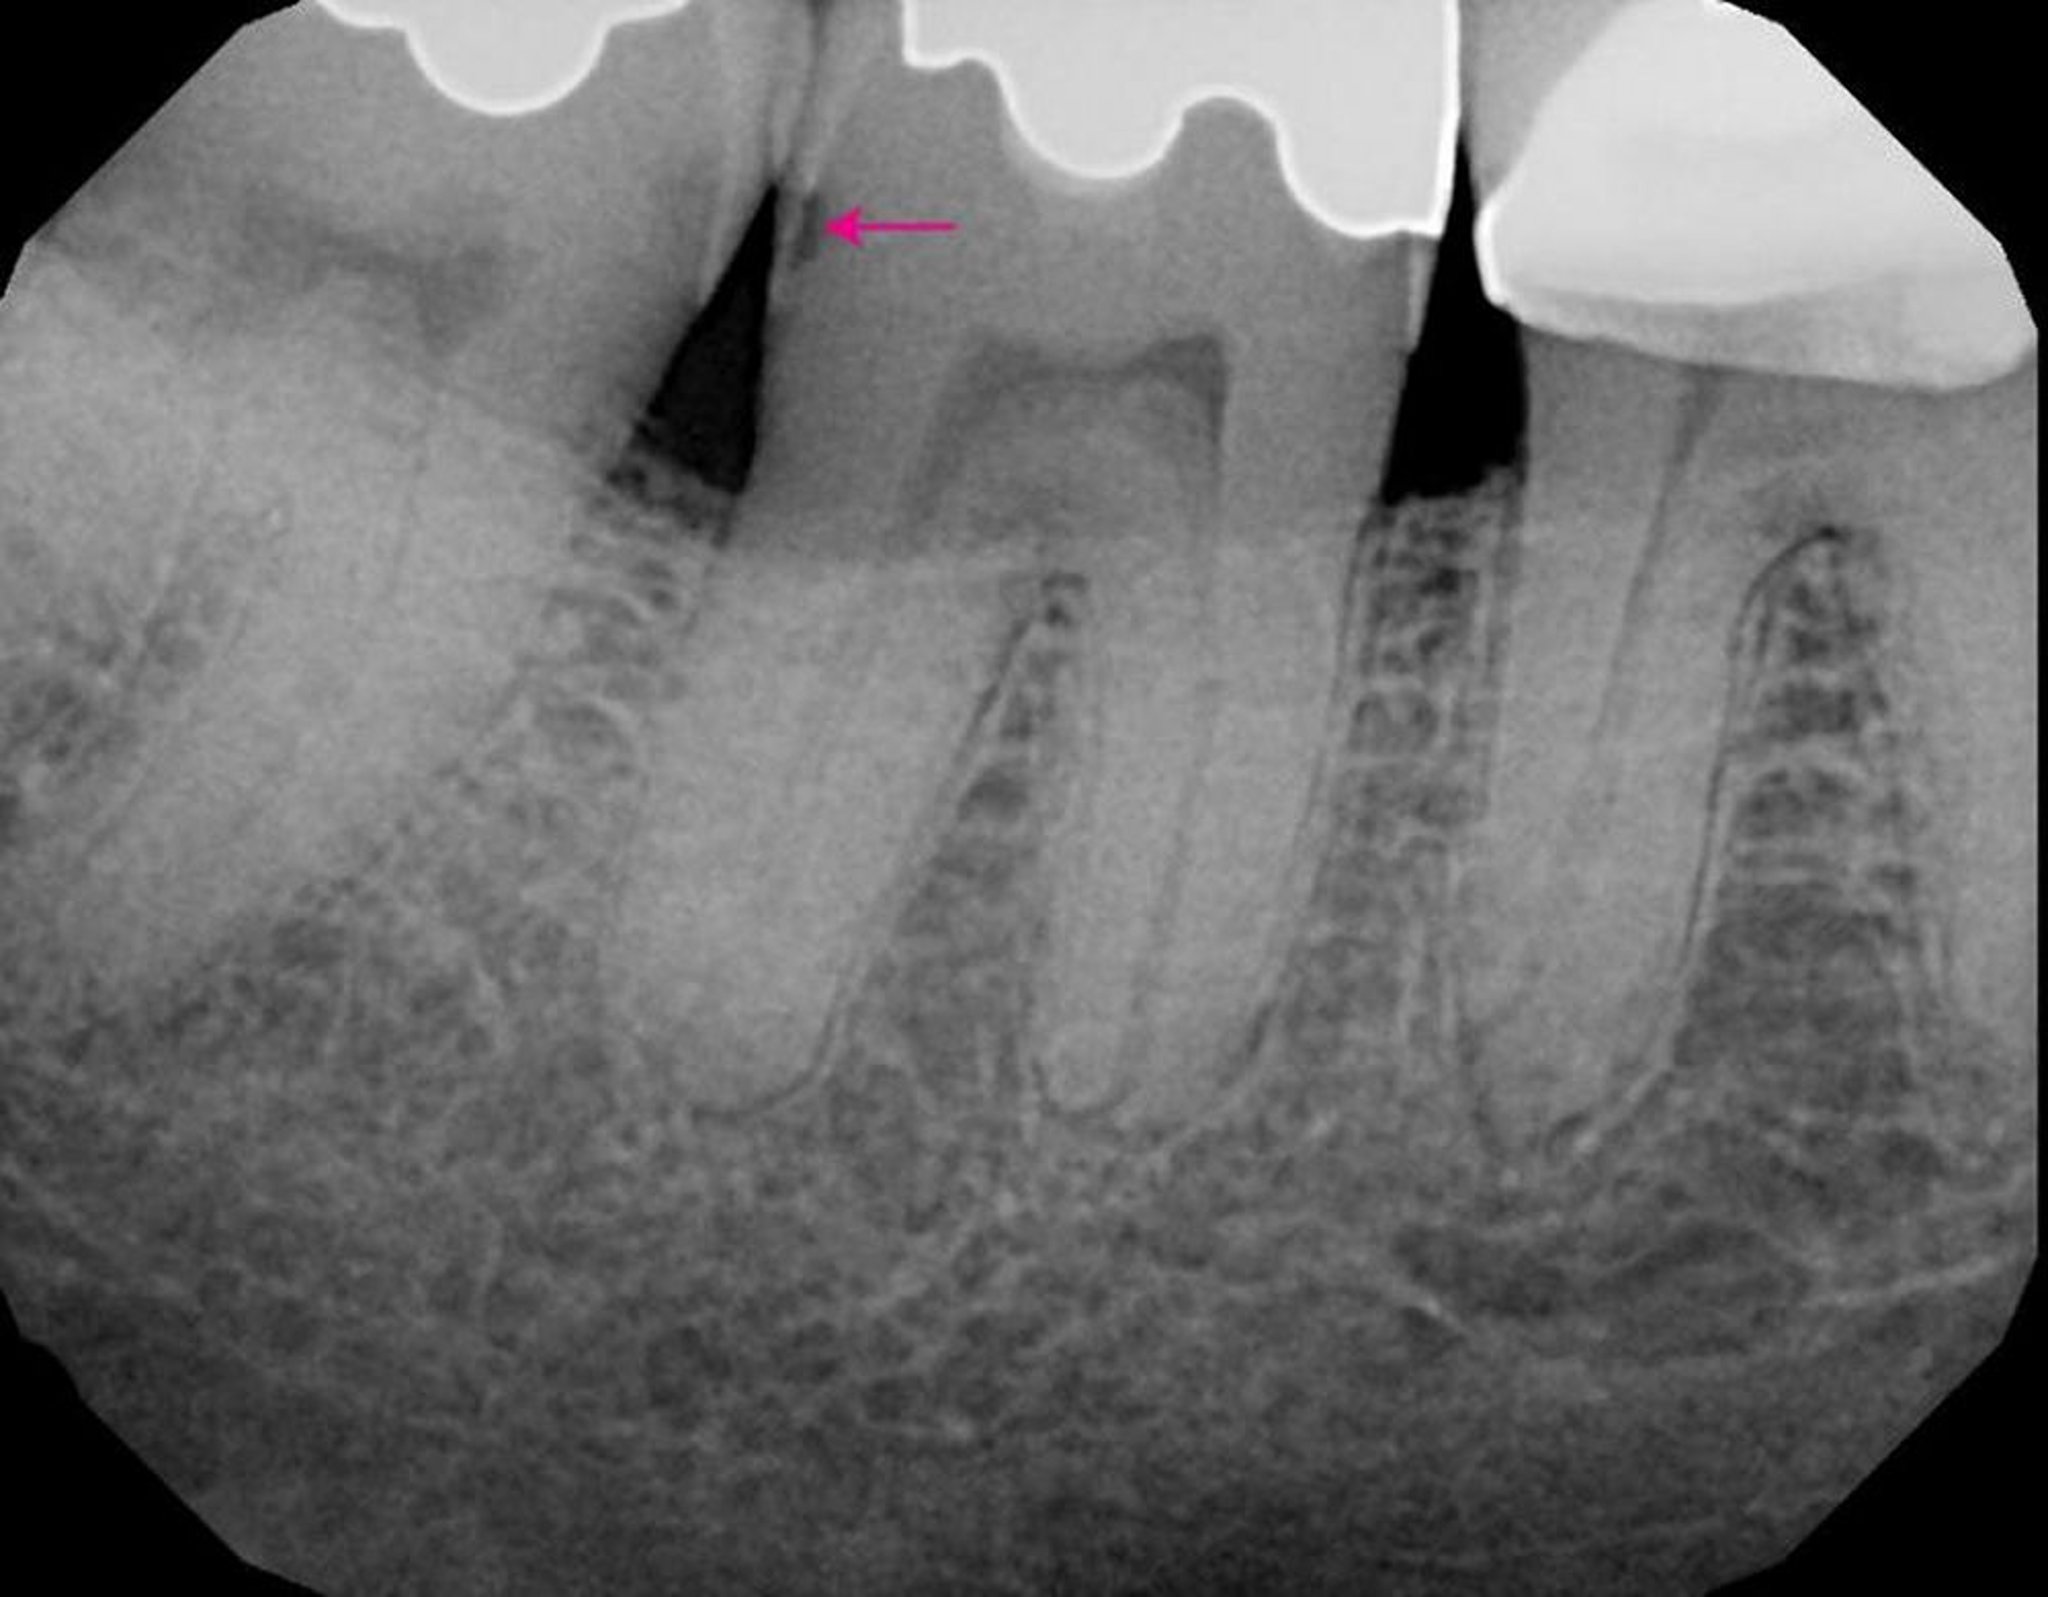

Cárie (radiografia)

Imagem fornecida por James Ubertalli, DMD.